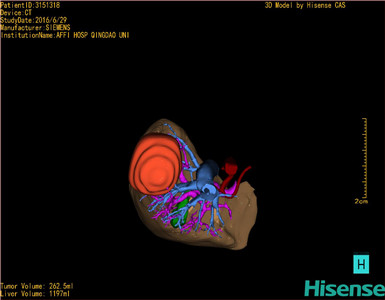

将0.625mm双源薄层CT资料的静脉期和动脉期Dicom格式文件导入海信CAS系统。

通过调节窗宽窗位调整CT序号,对肿瘤,肝实质,胆囊,下腔静脉,肿瘤,肝动脉、门静脉及肝静脉等进行三维重建;系统自动计算肿瘤体积和肝脏体积。

模拟手术操作,自动计算切除肿瘤体积。肝脏体积为1197ml,肿瘤体积为262.5ml,肿瘤体积为肝脏体积的21.9%,通过比对30-40岁正常肝脏体积为1323.35±298.47ml,通过术前模拟手术,精准判断切除后剩余肝脏体积能耐受,避免肝衰竭发生。

术前三维重建:

重建图片